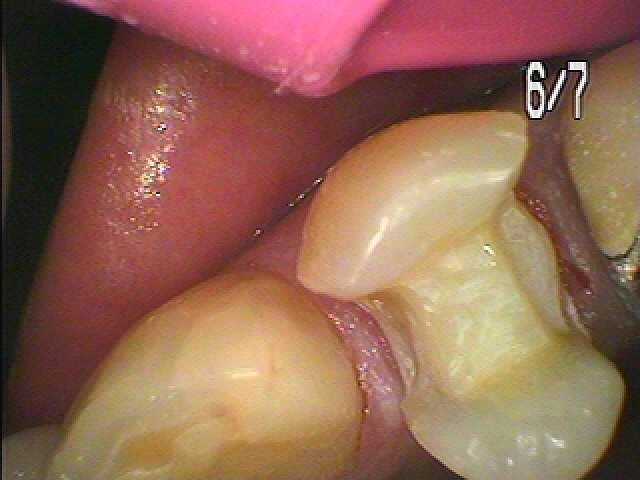

左上の4番部も銀歯を外して白いセラミックへやり変えていきます

虫歯を除去して白い樹脂にて覆罩しています

セレックセラミック(1本2万5千円)にて本来の歯の要旨を取り戻しました

銀歯と比べても綺麗で喜んでいただきました